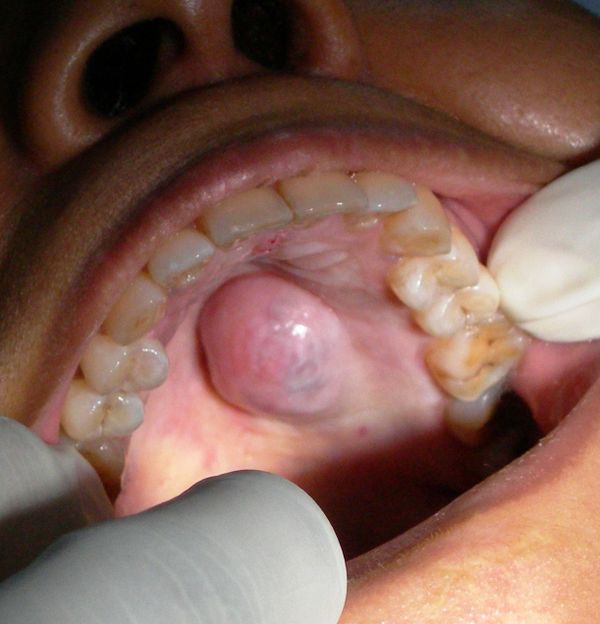

- Cyst and Tumour of Jaw

- Cyst & Tumour of Jaw/Face